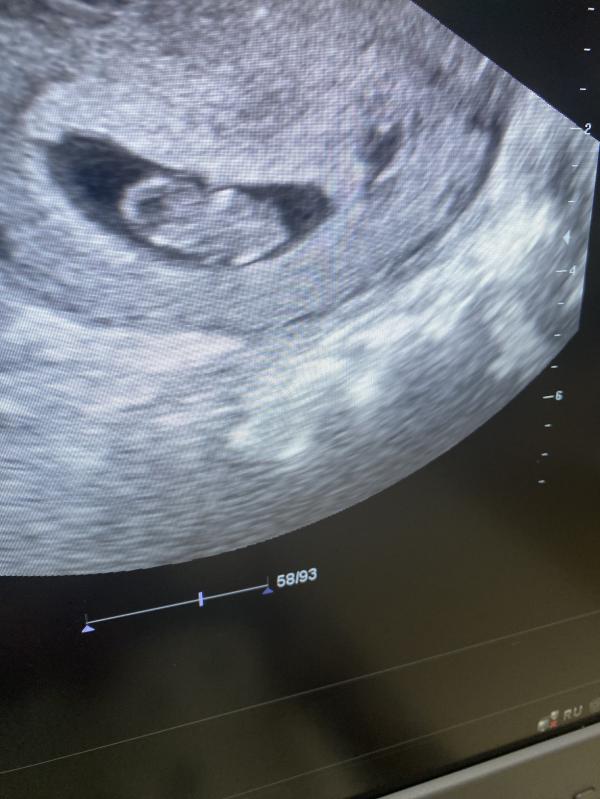

Здравствуйте. Опасно ли для малыша в плане дальнейшего развития то, что на УЗИ в 5 недель сказали что плодное яйцо слегка деформировано?